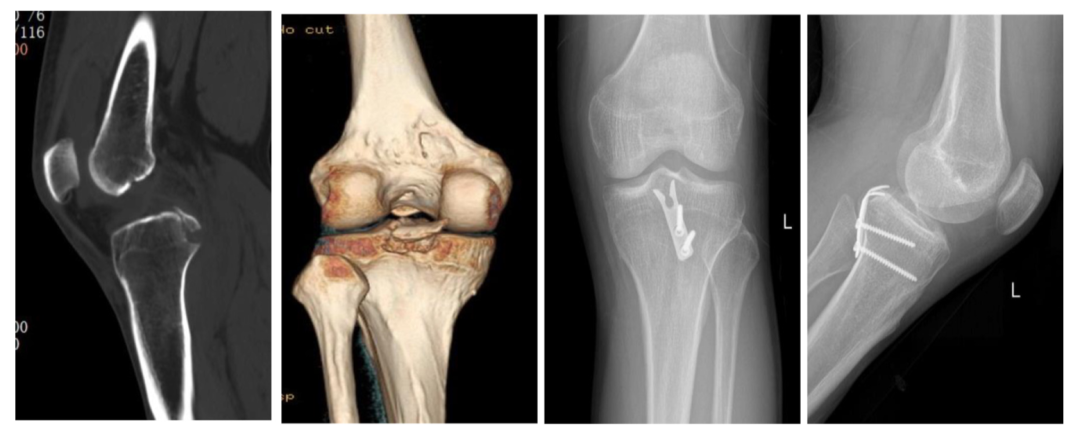

图4:35岁男性,钩钢板固定,术前术后影像片。